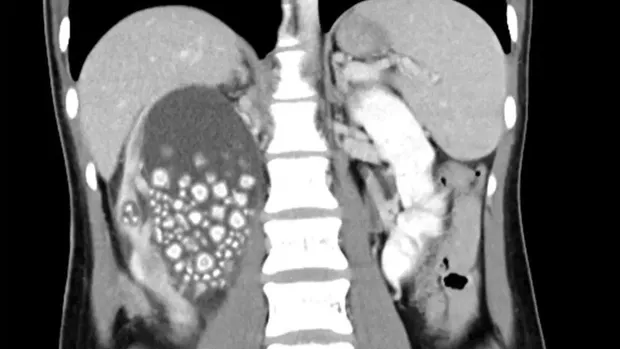

Melalui pemindaian ultrasonografi, dokter di unit gawat darurat menemukan bahwa ginjal kanannya bengkak berisi cairan dan terdapat batu ginjal di dalamnya. Hasil CT scan menunjukkan bahwa batu tersebut berukuran sekitar 5 mm hingga 2 cm, dan tes darahnya menunjukkan peningkatan jumlah sel darah putih.

Temuan batu ginjal di wanita yang doyan boba Foto: Chi Mei Medical Centre |

Dokter lalu memberinya antibiotik, mengeluarkan cairan dari ginjalnya dan melakukan operasi invasif minimal untuk menghilangkan lebih dari 300 batu ginjal.